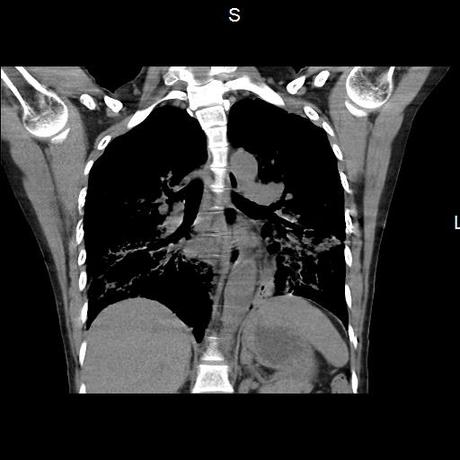

Se realiza volumen de tórax en fase simple, desde los opérculos torácicos hasta los hemidiafragmas, observándose:

El parénquima pulmonar con areas parcheadas difusas en vidrio despulido combinadas con otras areas hipodensas de baja atenuación debidas a atrapamiento aéreo y engrosamiento intersticial y zonas de fibrosis de predominio en lóbulos medios e inferiores de ambos pulmones.

- LOS HALLAZGOS PUEDEN ESTAR EN RELACIÓN A NEUMOPATIA INTERSTICIAL PROBABLE ETIOLOGIA HIPERSENSITIVA VS AUTOINMUNE/BACTERIANA/FUNGICA.